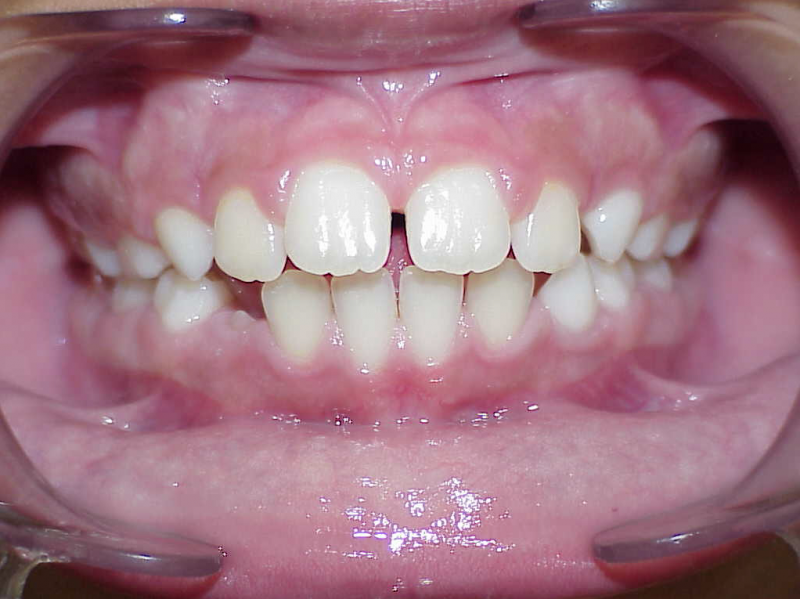

Behandeling Hajar

eindfoto

Beschrijving

Leeftijd bij aanvang: 9 jaar

1-6 maanden Bonded Hyrax in de bovenkaak, banden/slotjes in de onderkaak met Transforce

7-13 maanden: Twinblock

14-47 maanden: Volledig banden/slotjes in de boven-en onderkaak (omdat er hier blijvende kiezen ontbraken moesten er kiezen getrokken worden en de ontstane ruimtes gesloten, dit verklaart de langere behandeltijd)

Retentie fase: Wrap en C-CBar